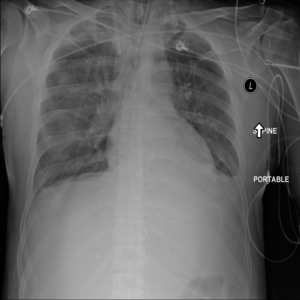

Figure 2: Examples of normal vs. abnormal images of considered datasets. Natural images: (first row) cars vs other classes of CIFAR10 dataset [1], (second row) digits “0” vs digits “1” – “9” of SVHN dataset [2]. Medical images: (third row) healthy tissue vs. tissue with metastases in H&E-stained lymph nodes images from Camelyon16 challenge [3], (fourth row) normal chest X-rays vs. chest X-rays with abnormal findings from NIH dataset [4].

Figure 6: Examples of normal (left) and anomaly (right) images of H&E-stained lymph node of Camelyon16 challenge [3] (top) and chest X-rays of NIH dataset [4] (bottom). We also showed the predicted anomaly score by the proposed method. The higher the score, the more likely to be an anomaly. Notice how the proposed method spots even the borderline cases.